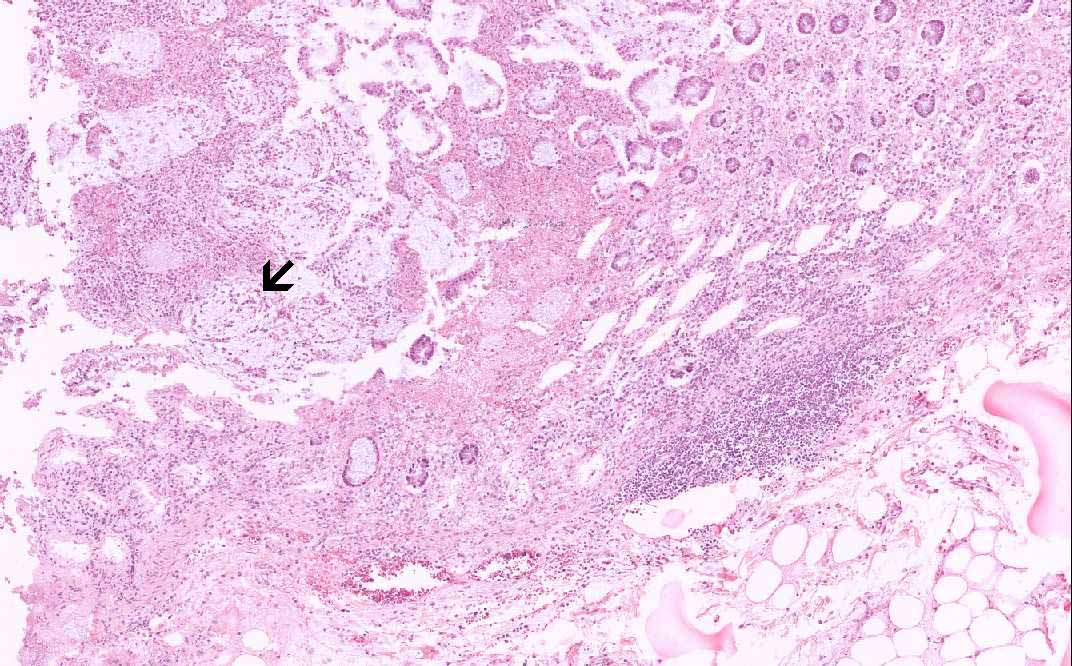

Area 1: The mushroom-like or volcano-like structures are well illustrated here. The overlying inflammatory substance is composed of neutrophils, karyorrhectic debris, and mucin.

• The submucosa (S) is rather edematous and the organization appears loose. The mucosa is rather irregular and is coated by a layer of inflammatory and necrotic substance. There is also patchy necrosis of the superficial aspect os of the mucosa. In the smaller lesions, the affected crypts become dilated and exude an inflammatory and necrotic substance reminiscent of a erupting volcano or mushroom-like structure (Area 1). There is extensive loss of colonic glands due to the necrosis. In the more severely affected areas, the inflammatory and necrotic substance  fuses together to form a pseudomembrane (Area 2). This pseudomembrane extends laterally to overlie adjacent normal appearing mucosa. The exudate is composed largely of karyorrhectic debris and neutrophils. Also the mucin has a tendency to alig with the necrotic debris and neutrophils in an interesting linear arrangement (Area 3).